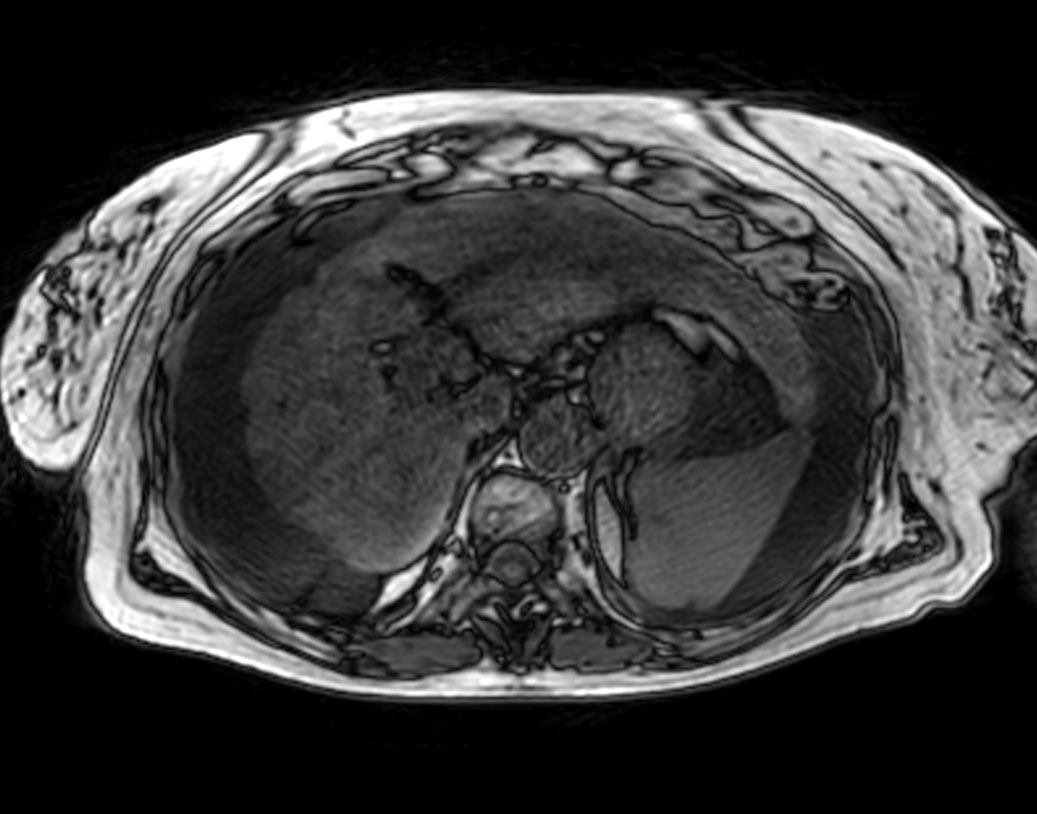

Axial T1w 3D VANE XD (Water only)